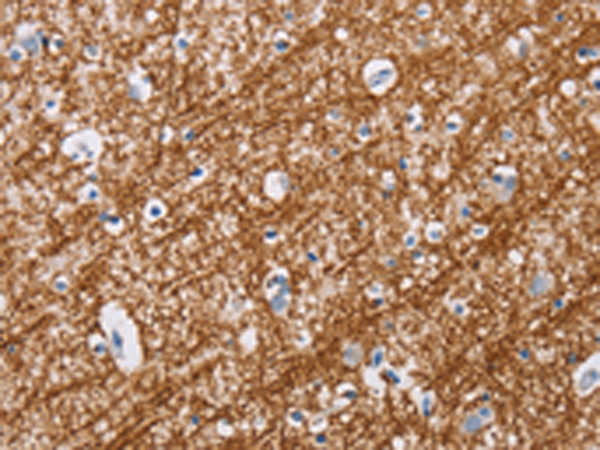

分类: 科研抗体货号: P07432别名: GMA; S-MAG; SIGLEC4A; SIGLEC-4A应用: WB,IHC反应种属: Human, Mouse, Rat